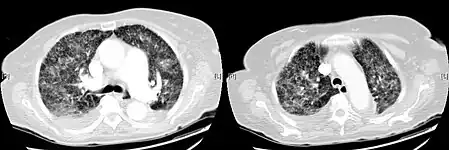

-

X-ray, showing bilateral interstitial infiltrates -

X-ray, showing extensive bilateral reticulo-nodular infiltrates -